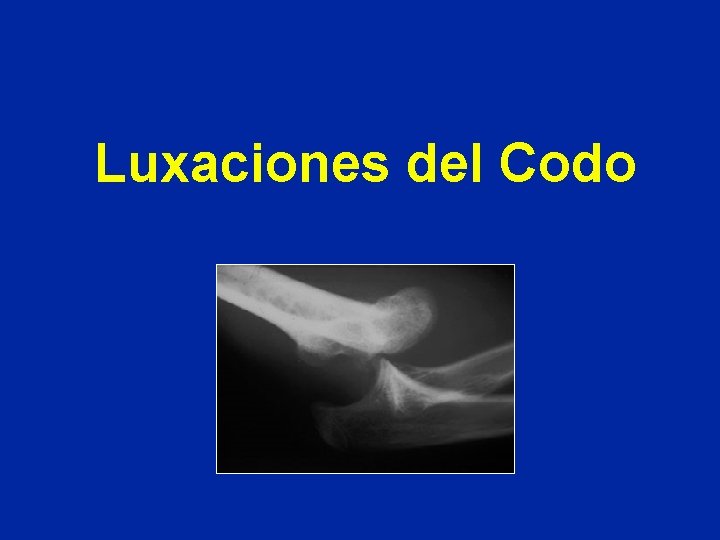

Luxaciones del Codo